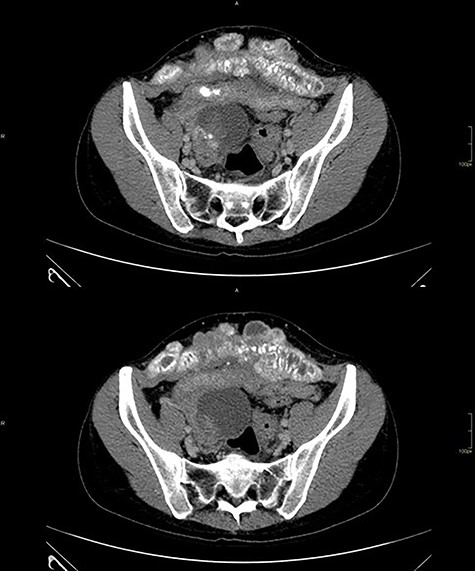

Computed tomography of the abdomen showed solid-cystic lesions in the pelvis (Fig. 2) and a massive expansive lesion in the AW, with soft tissue density and a volume of 334 cm3 (Fig. 3). Between the AW and the pelvic lesions, formation with soft tissue density, heterogeneous enhancement and calcifications are identified, measuring 12.5 × 2.5 cm in the major latero-lateral and anteroposterior axes, compatible with ‘omental cake’.

Abdominal wall CT with expansive lesion with soft tissue density, heterogeneous, with the appearance of a cluster of nodules, measuring 16.4 × 5.1 × 7.7 cm (334 cm3 volume) in the major latero-lateral, antero-posterior axes and longitudinal, respectively.